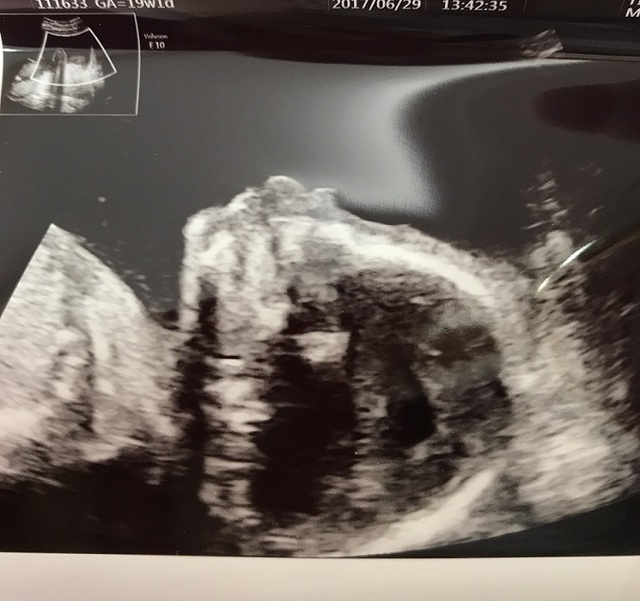

19週1日(19w1d・性別不明)|ゅんゅん さん(30歳)

エコー写真撮影時のエピソード:

横顔です!鼻も高そうだし、唇も可愛いです。今1歳10ヶ月の娘の時は、エコーでも鼻が低かったので低いまま産まれました(笑)

ちゃんとお姉ちゃんになれるか心配です。「赤ちゃんどこ?」と聞くと、必ず自分のお腹をさすり「ここ!ここ!」と言ってます。(笑)

でも、私が「赤ちゃんにチューして」と言えば、私のお腹にチューしてくれます。わかってるのか、わざとしているのか…